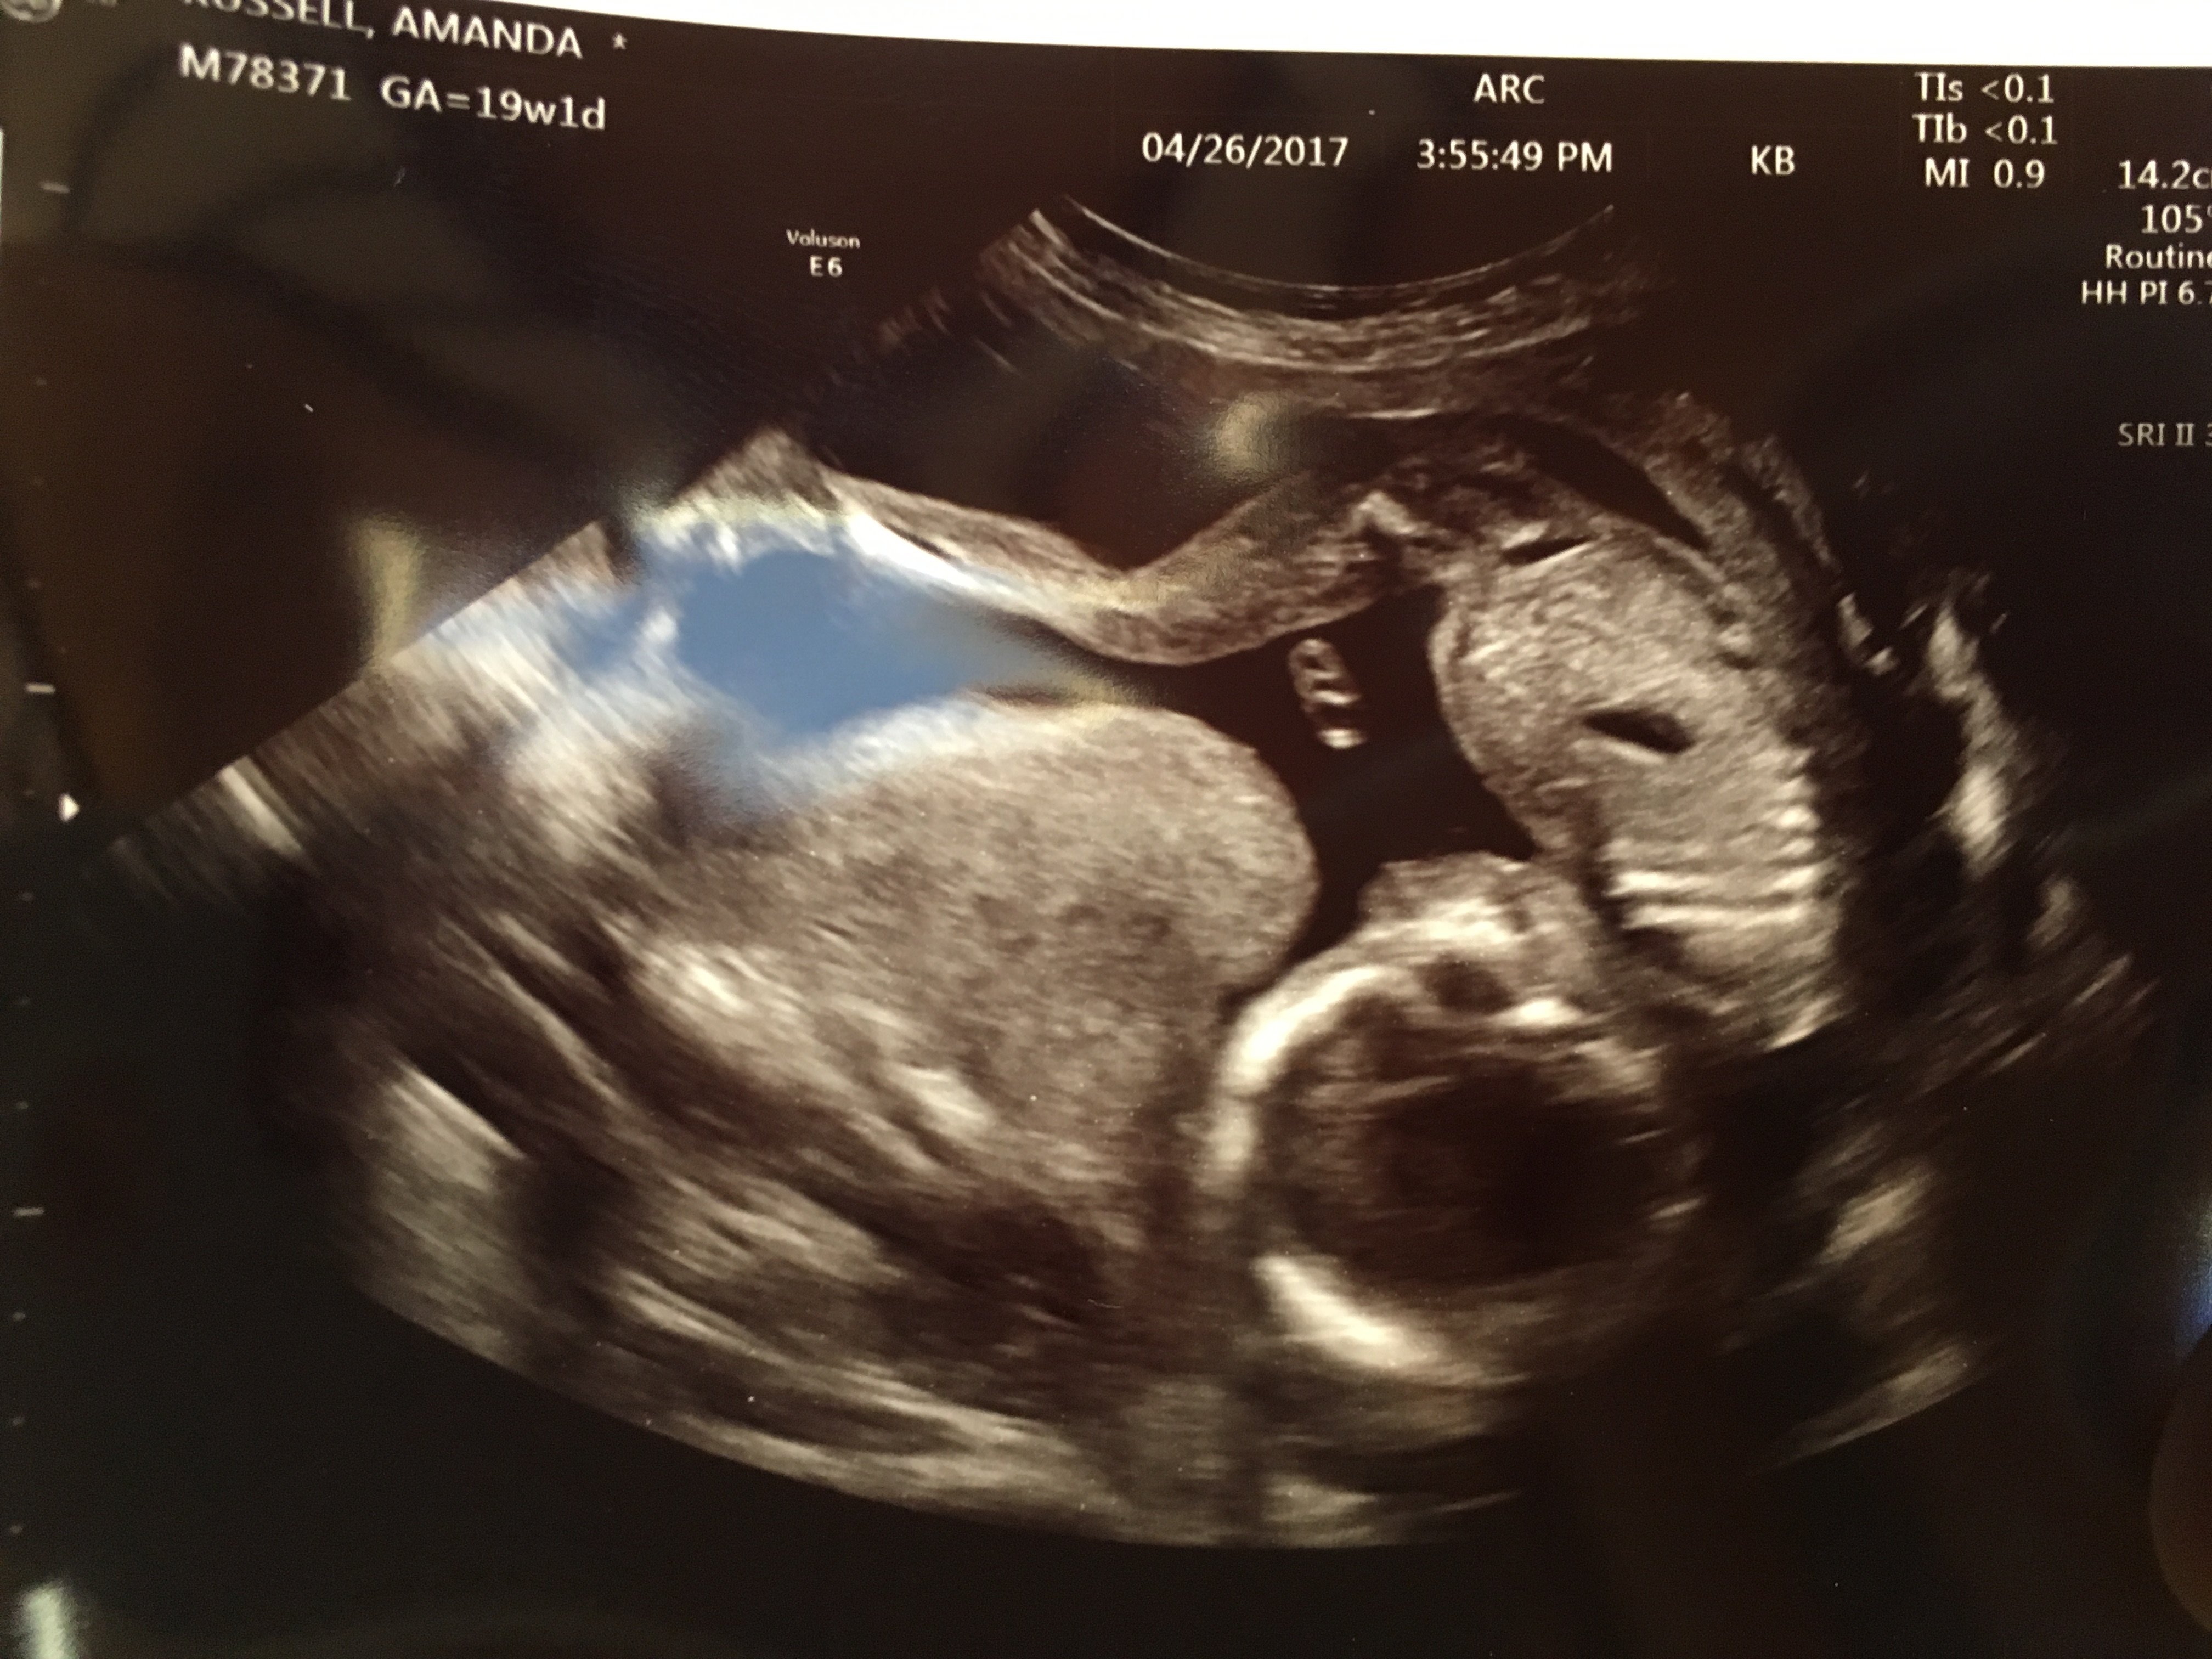

20 weeks and team green! Guesses please??

Was told maybe boy at 12 weeks but since then we decided to wait! Still would love guesses for fun....I'm not banking on anything don't worry ;)

Attachment 36046